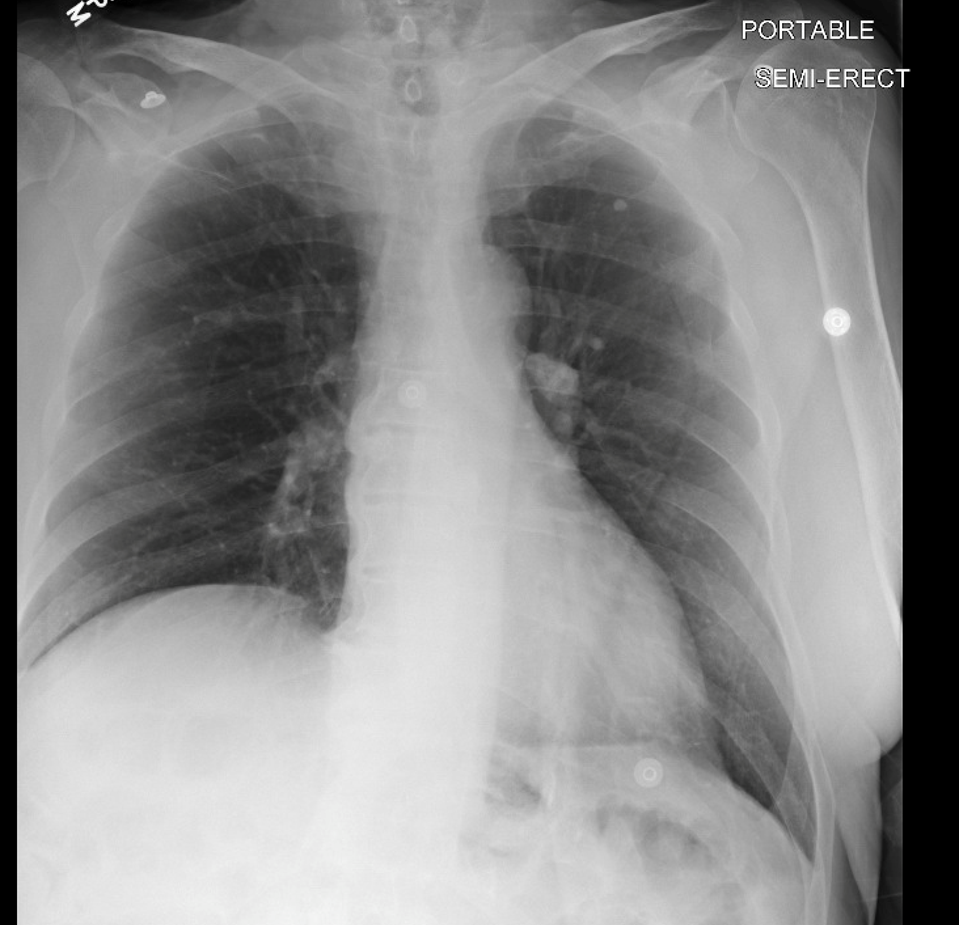

Tools required for chemoprophylaxis available by late 1940’s

Standardized skin test to reliably detect infection.

chest radiographs.

drugs for chemotherapy

- streptomycin, PAS (1944)